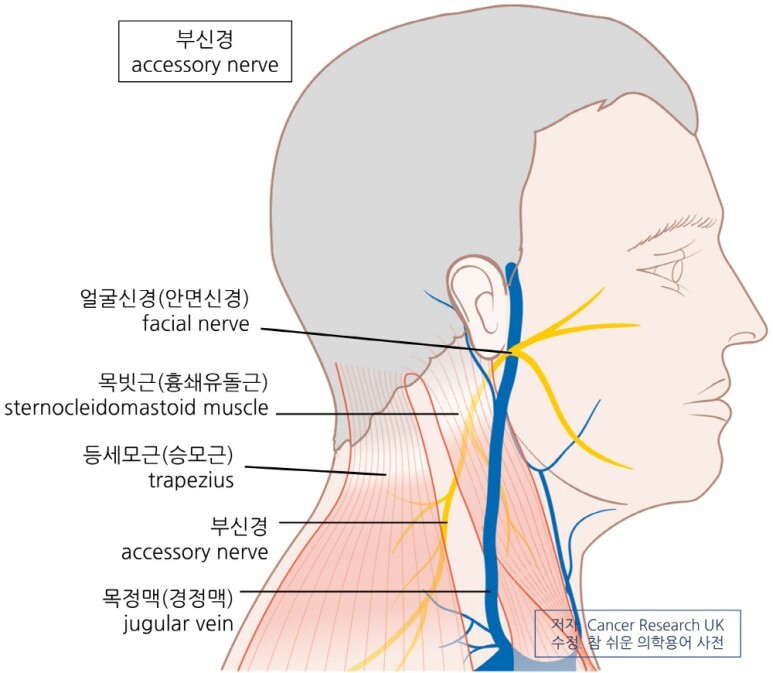

▶ 신경문제로 인한 근육이상

종종 신경의 문제가 원인이 될 수 있는데 대표적으로 긴가슴신경(장흉신경, Long thoracic nerve) 또는 척수부신경(Spinal accessory nerve), 등쪽어깨신경(Dorsal scapular nerve), 등의 손상으로 인한 전거근이나 승모근, 능형근의 문제가 생길 수 있습니다. 이 경우는 흔하지는 않습니다.

신경손상에 의한 경우의 치료

척수부신경(Spinal accessory nerve)의 문제나 장흉신경(long thoracic nerve)이 직접손상인 경우에 마비의 경우에, 심한경우에는 수술적으로 신경을 이어줄 수도 있지만, 심하지않은 손상의 경우에 장흉신경은 대부분 2년내 회복이 되므로 보존치료를 해볼 수 있습니다.